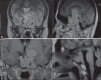

Results: Four out of 82 male MPRL had SM = 4.87%. Three consulted for SM symptoms. SM was confirmed in Infectious Diseases department, but only one had rhinorrhea. Hormonal assessment and cerebral magnetic resonance imaging pleaded for aggressive prolactinomas. After antibiotics, SM was sterilized. Then, MPRL were treated with bromocriptine, which normalized prolactin and reduced PT. SM never relapsed. The 4(th) case was hospitalized for a large multidirectional prolactinoma invading and/or arising from the skull base. He was operated on 3 times and then he was given Bromocriptine. After 3 months, he had rhinorrhea and then SM which was successfully treated by antibiotics. SM never relapsed after tumor reduction.